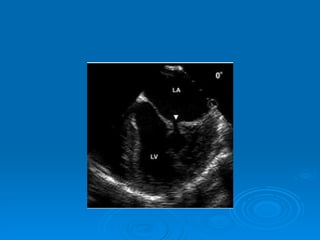

Echo-doppler Cardiaque Echographie bidimentionnelle: Épaississement de la valve Diminution d’ouverture valvulaire Aspect caractéristique en genou fléchi de la GVM Mesure de la surface mitrale Recherche de calcifications Recherche de thrombis intra auriculaire gauche Dilatation de OG Etude de l’appareil sous valvulaire

Echo-doppler Cardiaque Echographiebidimentionnelle: Épaississement de la valve Diminution d’ouverture valvulaire Aspect caractéristique en genou fléchi de la GVM Mesure de la surface mitrale Recherche de calcifications Recherche de thrombis intra auriculaire gauche Dilatation de OG Etude de l’appareil sous valvulaire